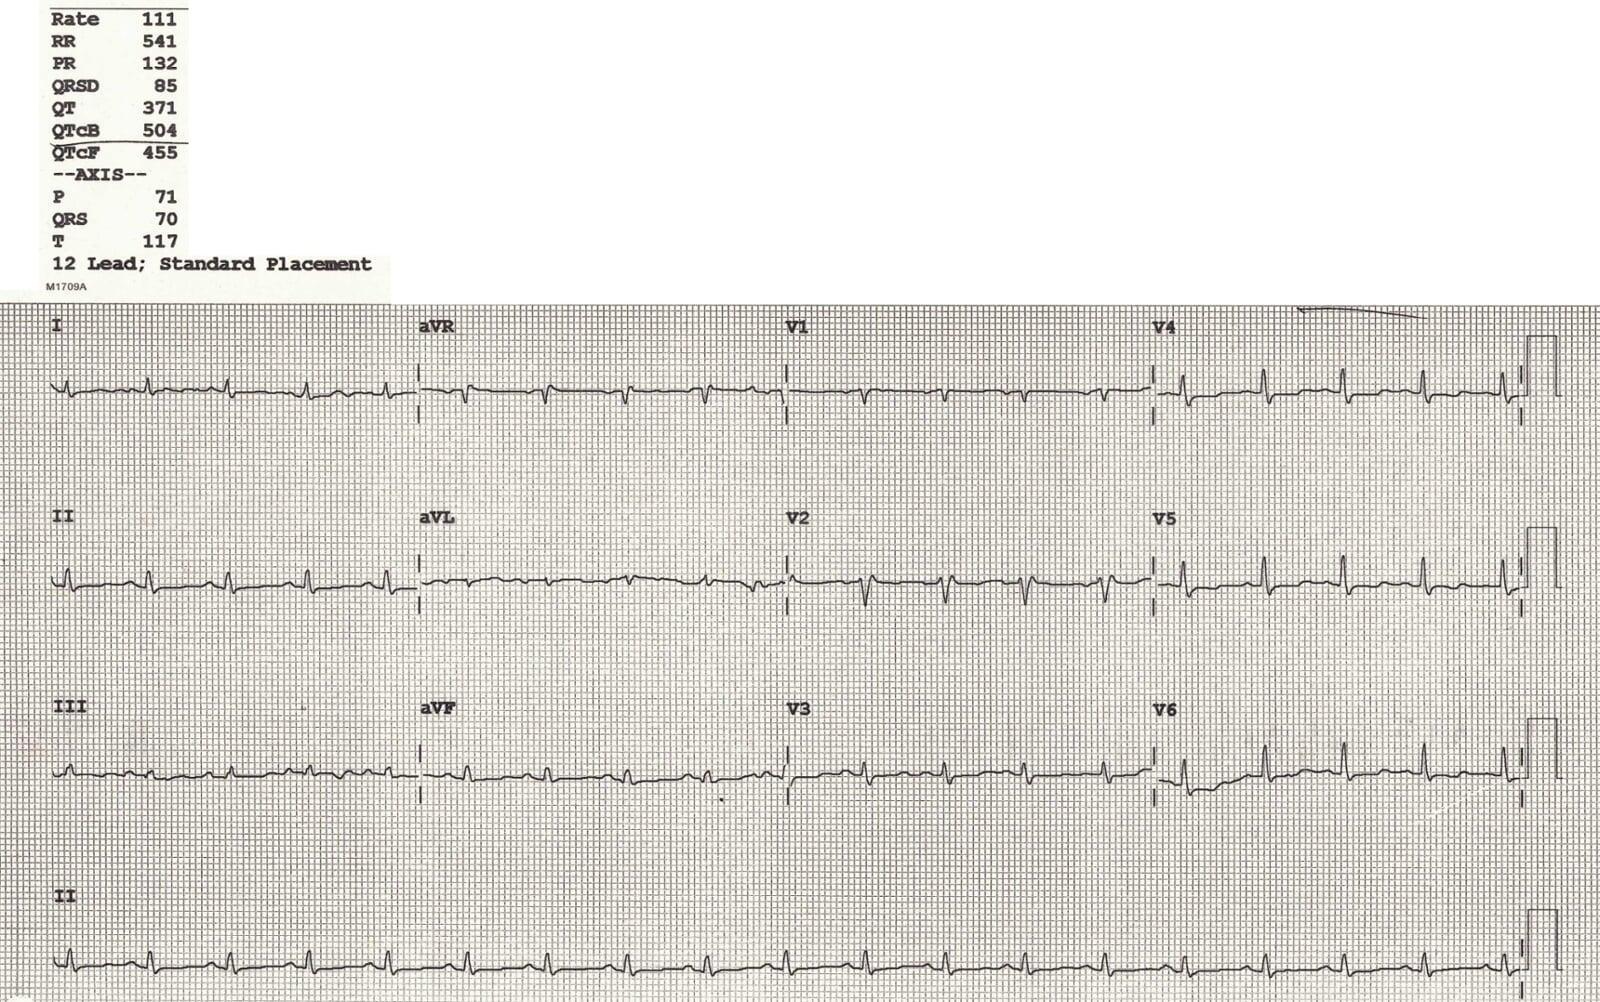

This was the ECG of the patient,

The ECG showed two critical abnormalities:

1. Prolonged QTc

2. Low voltage ECG

● Likely related to chemotherapy

● Electrolytes were not severely abnormal

Definition:

● Limb leads (I + II + III) total height < 15 small squares, and/or

● Precordial leads (V1–V3) total height < 30 small squares

Classic ECG Triad of Massive Pericardial Effusion:

● Low Voltage ECG

● Tachycardia

● Electrical Alternans(not seen in this case)